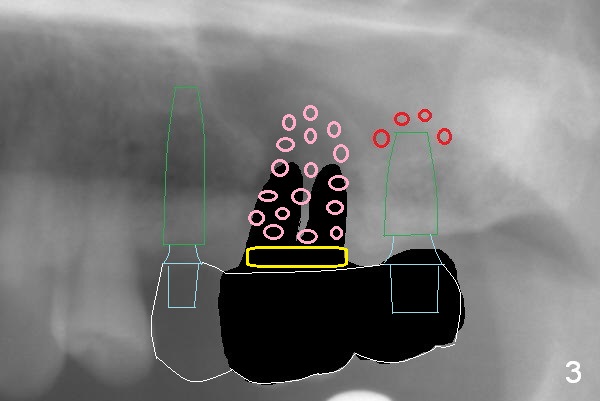

The 72-year-old man will return for #13-15 implantation after that at #2/4 and 28. There is severe wear in the cingula of the upper anterior teeth due to posterior collapse (several missing teeth, residual root and failing restoration, Fig.1). Prior to removal of the cantilever bridge (#14.15), an implant is placed at #13 (Fig.2). If the defect at #14 is too large after extraction, an implant is placed at #15 with an immediate provisional bridge (Fig.3 white line). Otherwise a large implant (possibly Tatum tapered) will be placed at #14 (Clindamycin) with splinted immediate provisional (Fig.4). Allograft is expected for sinus lift at #14 and 15 (Fig.3,4 red circles with Osteogen in 3:1 ratio). For socket preservation at #14, mix equal amount of allograft and Osteogen (Fig.3 pink), followed by Collagen plug (yellow) and the pontic of the provisional bridge. Prepare PRF (3-4 tubes of blood, one of them to be made for a plug).